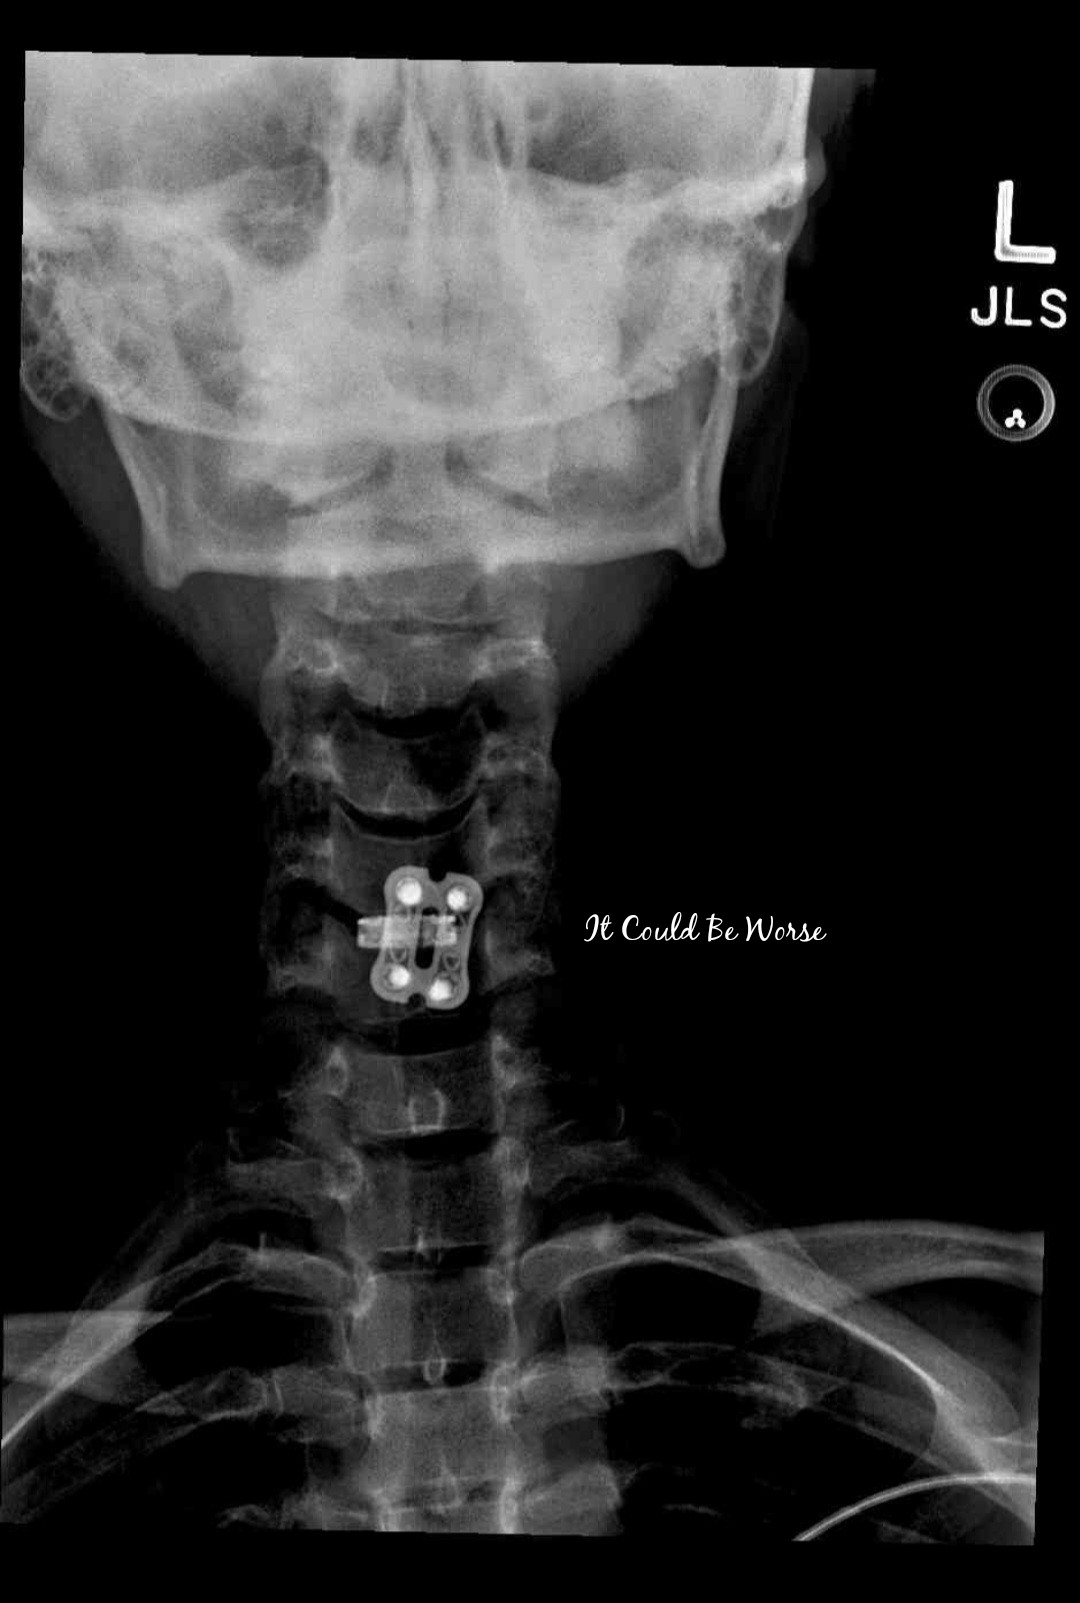

Hooray for finally getting to see my new hardware!

I was a little bummed last week when I didn’t have X-rays taken for my two-week post-op appointment. I wanted to see where the titanium was placed and what it looked like but they told me I would have to wait and get a set done by week 4 or 6.

They had mentioned that they had taken some X-rays during my procedure – but I wasn’t seeing them in my medical chart, I could only find fluoroscopy images of pre-hardware.

I checked my chart today to see if they had updated it – and there were two images of hardware from the ACDF surgery.

It makes me feel a little better now that I can see what was placed and where. I’m hoping this hardware stays in place (unlike my rib plating) and I like having these images to refer back to in the future.